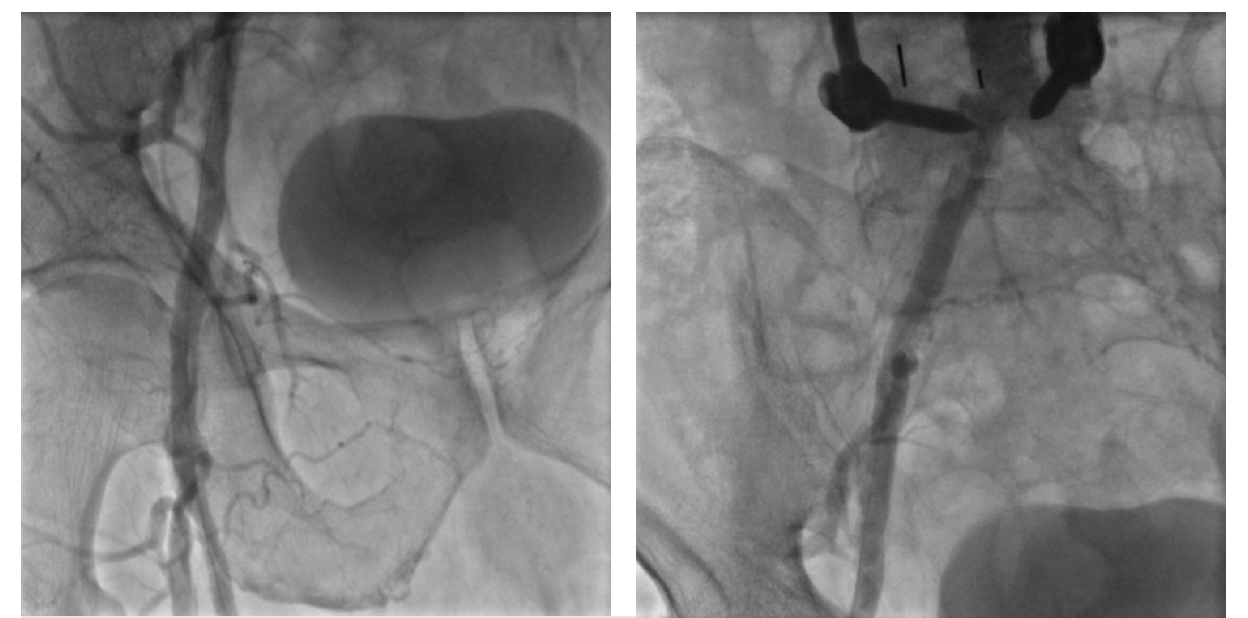

Peripheral angiography revealed moderate abdominal aortic aneurysm, severely calcified and stenotic right common as well as external iliac artery stenoses, and total occlusion of the left CFA (Figure 1). Collaterals were noted to reconstitute to the distal left CFA. No opacification was noted in the left common or external iliac arteries via collateralization. The right CFA was also noted to have a severely calcified mid-vessel stenosis. The remainder of the infrainguinal vessels were free of significant stenosis. A plan was made for right iliac and CFA intervention with surgical right-to-left femoral-to-femoral bypass grafting with left common femoral endarterectomy.